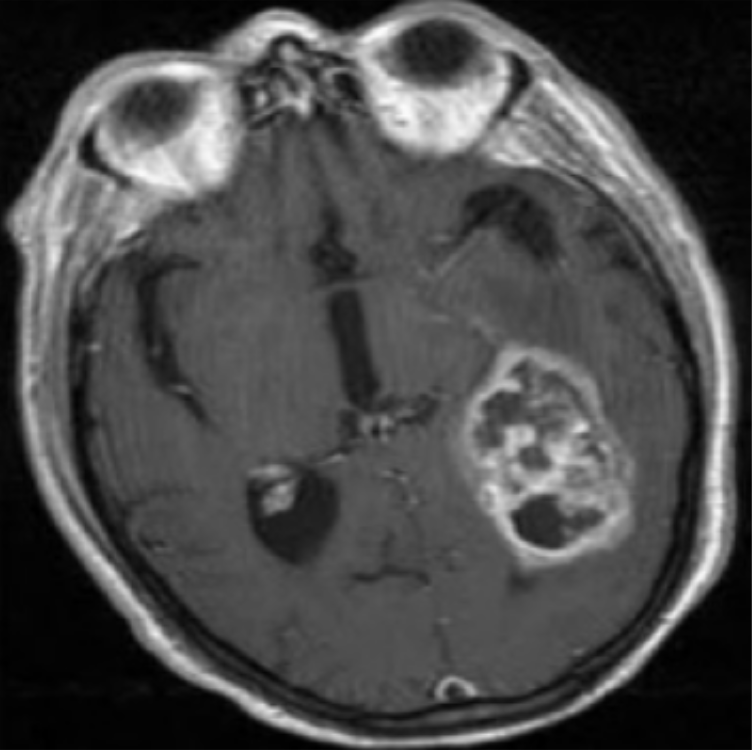

Refer to caption

(a) Glioma

(b) Meningioma

(c) No-tumor

(d) Pituitary

Figure 1: Sample MRI images from the 7K-DS dataset (Glioma, Meningioma, No Tumor and Pituitary).